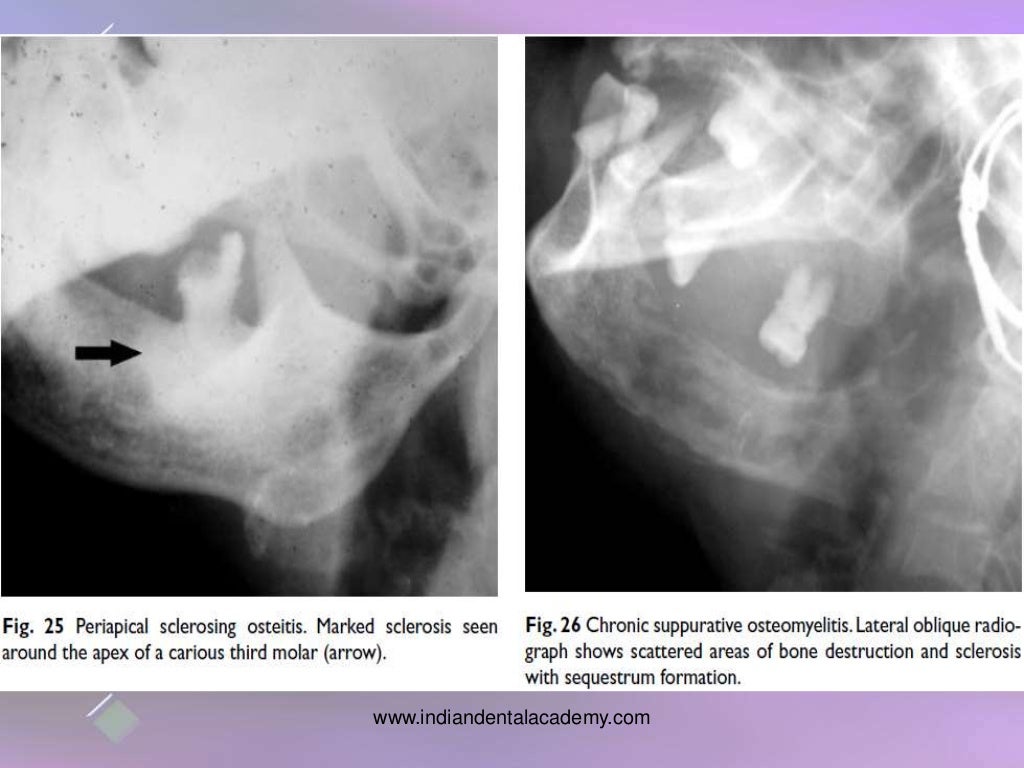

osteomyelitis of jaw bones / dental implant courses by Indian dental Osteomyelitis From Dental Implants osteomyelitis of the jaws following dental treatment is a rare. the past few years have seen a progressive increment in the number of osteomyelitis cases associated with dental implants,. Five cases of mandibular osteomyelitis emerging in dental implant insertion sites are presented. the knowledge of the real impact of osteomyelitis on the outcome of implant therapy and. Osteomyelitis From Dental Implants.